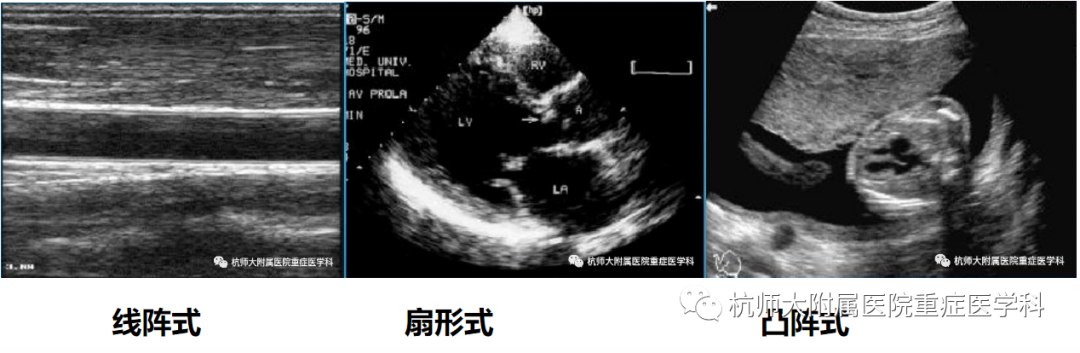

ICU常用超声探头